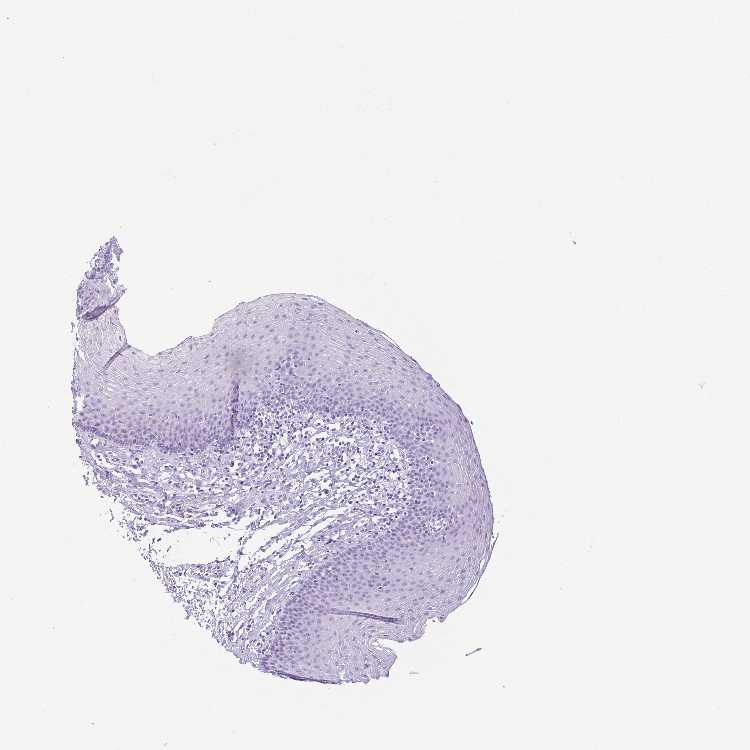

ESOPHAGUS - Antibody stainingi

Antibody staining in the annotated cell types in the current human tissue is reported as not detected, low, medium, or high, based on conventional immunohistochemistry profiling in selected tissues. This score is based on the combination of the staining intensity and fraction of stained cells.

Each image is clickable and will lead to virtual microscopy that enables deeper exploration of all samples and also displays staining intensity scores, fraction scores and subcellular localization as well as patient and tissue information for each sample.

Antibody HPA044730Antibody HPA054184

Squamous epithelial cells Not detectedMedium